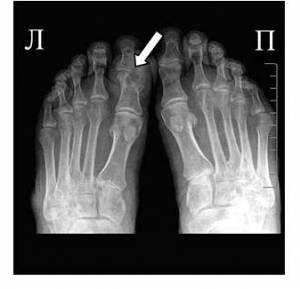

На фото симптом «пробойника» на кости первого пальца ноги

- Рентген-диагностика воспаленных суставов.

| Рентгенография сустава | Изменения хрящевой поверхности на фоне сужения суставной щели |